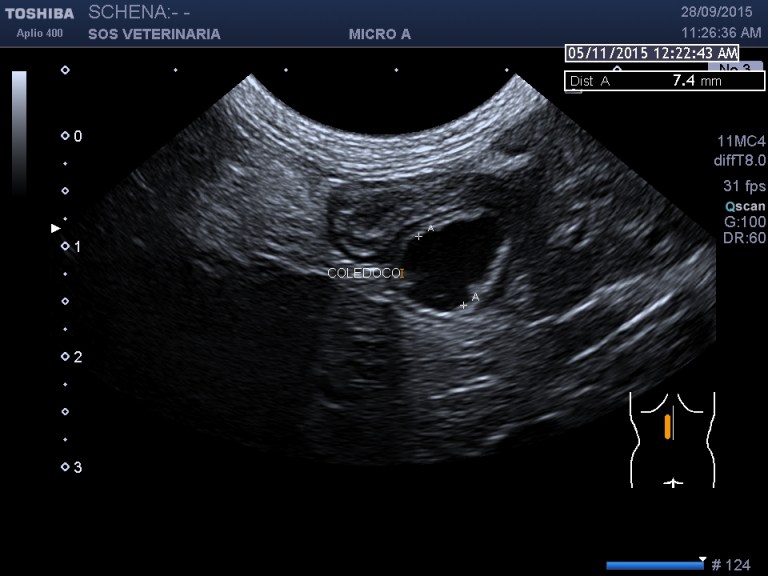

dilatazione del coledoco che decorre rettilineo

dotto biliare e vena porta dotto pancreatico ectasico  duodeno

evidente la dilatazione e l’ispessimento   della parete  a carico di coleciste e coledoco con   formazione presfinterica di un ampolla ectasica simil diverticolo probabilemente secondaria alla cronicita’ del processo ,non si evidenziano ostacoli calcolotici o neoformazioni occludenti  il deflusso intra o extraluminali e a livello della papilla , il pancreas si presenta omogeneo ipoecogeno iperplastico trama vasale  ben evidenziabile .